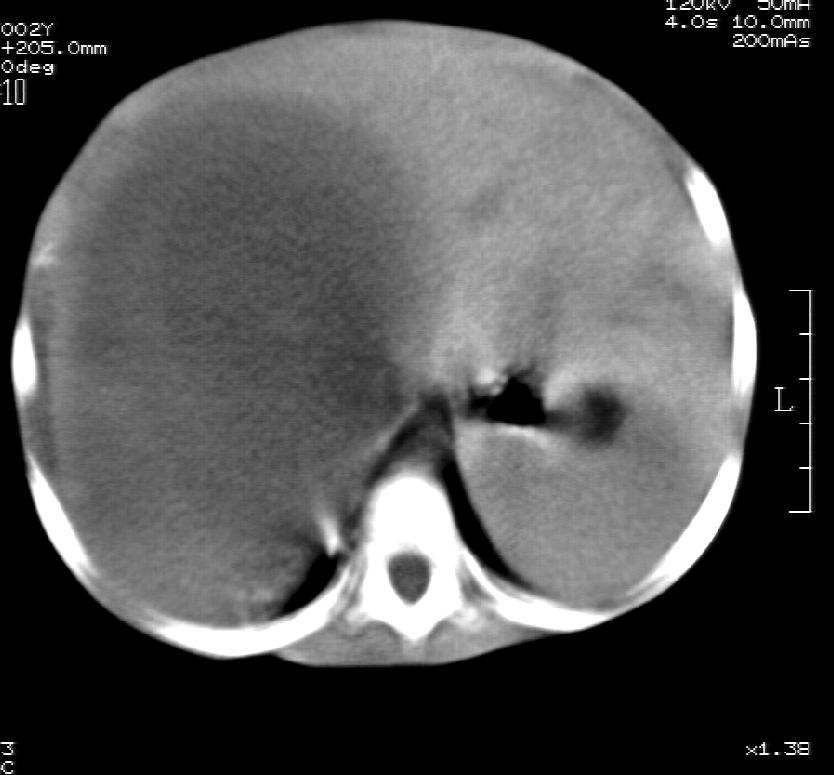

右肾巨大囊性占位病变,其内密度不均,正常肾结构消失,肝脏,肾上腺及肠管等受压移位。双肺内多发大小不等的结节及块状影。考虑右肾母细胞瘤伴双肺多发转移。

肾母细胞瘤(wilms),系儿童最常见的恶性肿瘤,好发于3岁以下儿童,瘤体较大,主要由胚胎性肉瘤样细胞和上皮样细胞构成,临床以腹部肿块;血尿和高血压为主要体征。

ct表现:密度不均匀的大肿块存在;出血和坏死。与神母鉴别点:wilms易向颅脑转移,而神母易往肺转移。

ct表现:密度不均匀的大肿块存在;出血和坏死。与神母鉴别点:wilms易向肺转移。而神母易往颅脑转移.